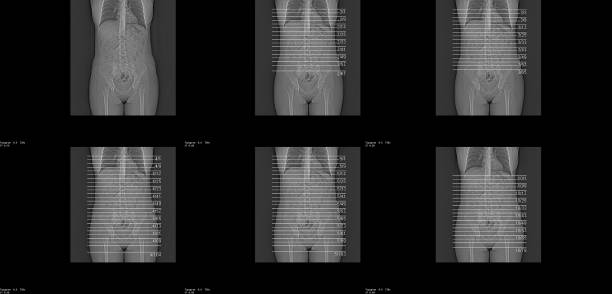

Diagnosis

If you have a femoral hernia you should receive medical attention quickly as a high risk of complications that may be serious.

Your health expert will examine the area, and they may also order imaging tests, such as MRI scan, ultrasound, or CT scan. These help them see the position of the internal tissues and distinguish between inguinal and

femoral hernias.